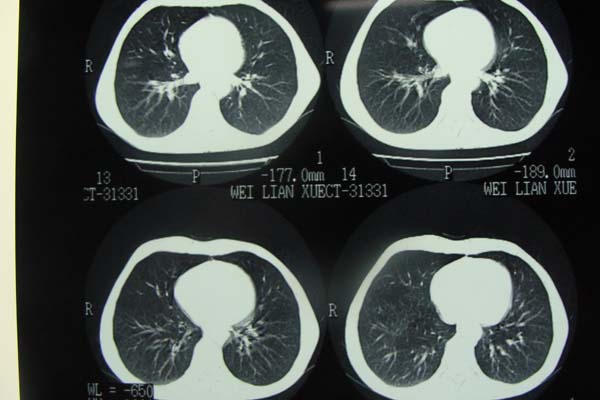

以下是引用pujunzhi在2009-6-21 21:48:00的发言:[br]右肺上叶后段见一空洞性病灶,灶周有渗出即晕征,右肺门肿大---可考虑感染性空洞和癌性空洞,先抗炎抗痨后复查并完善相关检查。有癌性空洞伴肺门淋巴结转移的可能。